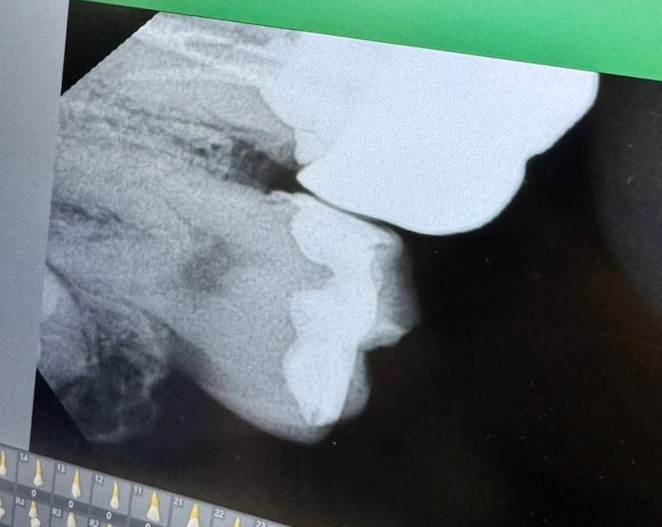

Mira12345 Опубликовано 25 сентября, 2025 Поделиться Опубликовано 25 сентября, 2025 Здравствуйте! Подскажите, пожалуйста, нормально ли поставили коронку? Болит под коронкой при жевании,зуб депульпированный периодонтита нет каналы пролечены хорошо, боль не острая, боль больше вглубь уходит. Иногда болит иногда нет. Врач говорит что все хорошо, но дискомфорт и боль временами все равно есть. Что это может быть, проблема в коронке или самом зубе? Ссылка на комментарий

red_butler Опубликовано 28 сентября, 2025 Поделиться Опубликовано 28 сентября, 2025 Здравствуйте, снимок не информативен. покажите Кт и фото во рту. Ссылка на комментарий